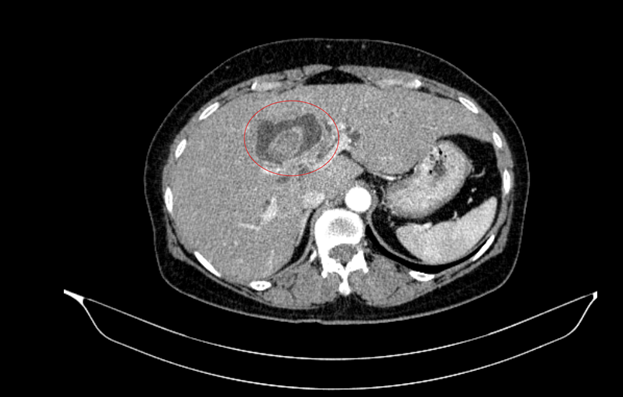

Hình 1. Hình ảnh sỏi đường mật tạo ổ áp xe gan – đường mật gan trái( vòng tròn màu đỏ). Giãn nhẹ đường mật trong gan hai bên. Dày thành nhẹ ngã ba đường mật trên phim chụp cắt lớp vi tính.

Tháng 01/2025 Bệnh nhân ở nhà xuất hiện mỏi, vàng da, ngứa kèm sốt kéo dài một tháng, đợt này đau bụng mạn sườn phải, kèm vàng da tăng dần, đi khám ở bệnh viện tuyến dưới, siêu âm có sỏi đường mật gan trái kích thước 22×41 mm. Bệnh nhân được chuyển đến bệnh viện Bạch Mai và được chụp CT ổ bụng phát hiện, kết quả: Gan có kích thước bình thường, bờ đều, nhu mô hạ phân thuỳ IV có ổ tổn thương dạng dịch kích thước 40x53mm, trong có sỏi lớn đường kính 35mm.